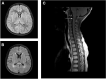

Autoimmune glial fibrillary acidic protein astrocytopathy is a novel form of autoimmune meningoencephalitis related to GFAP autoantibodies. This condition is still being characterized, and few pediatric patients have been identified. Here, we report three patients presenting with fever, nausea, and headache, following progressive disturbance of consciousness, limb weakness, dyspnea, or urine retention. MRI analysis revealed that T2-hyperintense lesions, or enhancement of the meninges and spinal cord. CSF and serum analyses revealed they were positive for GFAP antibody, confirming GFAP astrocytopathy diagnosis. Treating the patients with IVIG, with or without intravenous steroids, gradually improved their clinical symptoms. Our findings indicate that GFAP astrocytopathy should be considered in children who are clinically diagnosed with meningoencephalitis, whether or not myelitis is present, and if the MRI reveals enhancement of meninges or spinal cord, T2-hyperintense lesions, or a pattern of linear perivascular gadolinium enhancement. Suspected cases should be tested for GFAP antibody as soon as possible because these patients may benefit from immunotherapy.